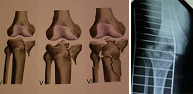

The knee joint engages the lower end of the femur and upper tibia. Other anatomic structures such as meniscae, ligaments and cartilage surface are important parts of the knee joint which make treatment one of the more complex surgeries of the skeleton. The bone injuries at this level are produced by high energy trauma from road traffic accidents, falls from great heights to sports such as soccer, downhill skiing, rugby, martial arts, motorsports, etc. The huge range of injuries at this level requires a thorough study before making treatment decisions. Recent advances in arthroscopic technique have led to the creation of minimum wound treatment where an optical camera is introduced allowing the repair of the injury under direct vision.